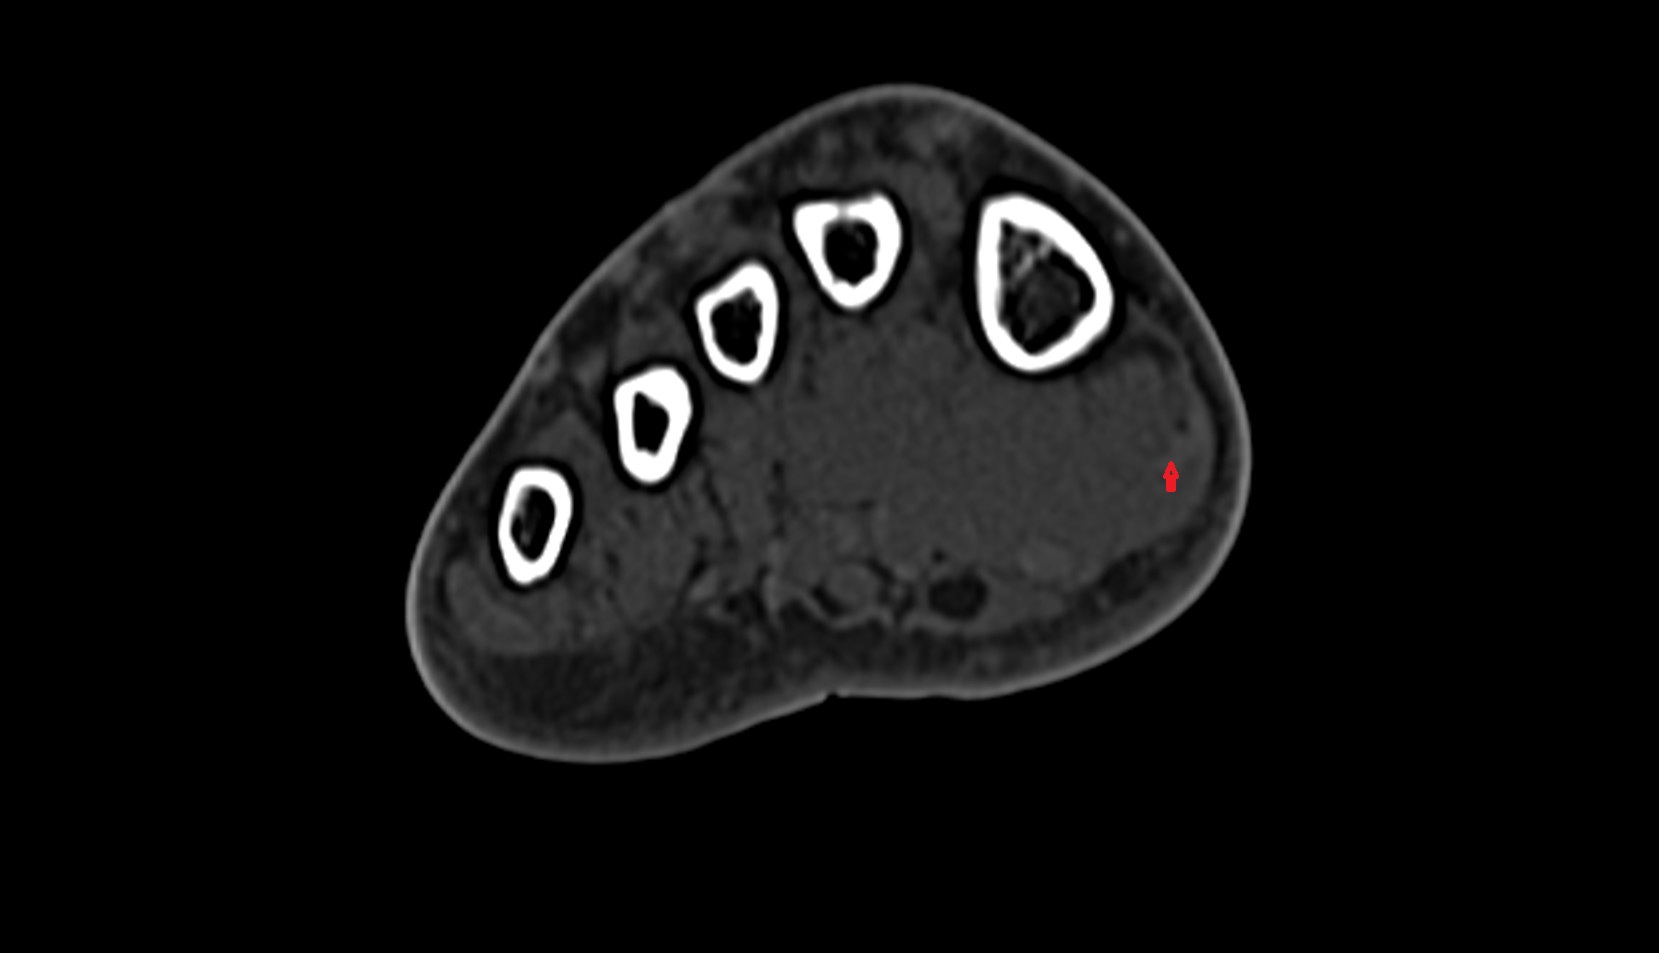

- Talus

- Calcaneus

- Cuboid

- Lateral cuneiform bone

- Medial cuneiform bone

- Intermediate cuneiform bone

- Interosseous membrane (middle tibiofibular ligament)